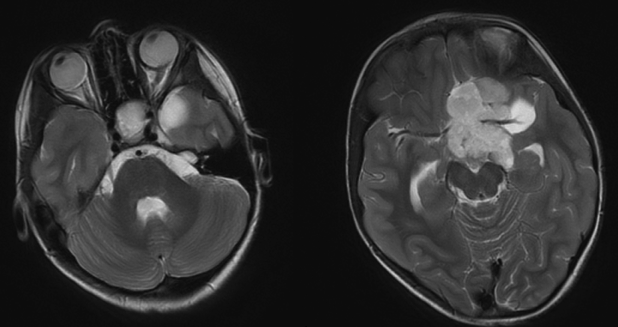

大脑的磁共振成像(MRI)扫描,显示高质量在鞍和蝶鞍部占位(图2)。病人接受了内镜活检(图3),这证实了诊断视神经通路的神经胶质瘤(星形细胞瘤),患者被转到遗传学部门评估1型神经纤维瘤病(NF1)的其他特征,但没有发现。她被转到肿瘤科,开始化疗,包括每周长春新碱和卡铂。在治疗期间,患者接受了一系列眼科检查和神经影像学检查。

图2:轴位t2加权MRI图像显示在蝶鞍和鞍上区域有一个大的、实性的、囊性分叶状肿块。